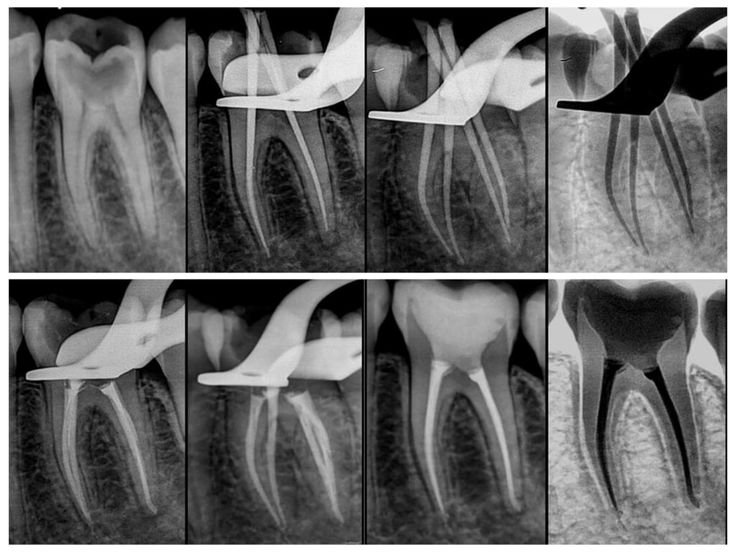

β€’Root Canal Therapy: Cleaning and sealing the tooth to eliminate infection.